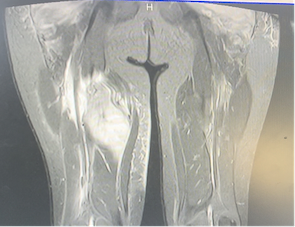

Viene presentato il caso di un bambino di 10 anni, giunto alla nostra attenzione per coxalgia, febbre intermittente e difficoltà alla deambulazione da circa 4 giorni. In anamnesi attività fisica intensa nei giorni precedenti e una ferita al ginocchio destro non correttamente disinfettata. In reparto si presentava in condizioni cliniche discrete, febbrile e con multiple tumefazioni agli arti inferiori dolenti alla palpazione. Gli esami di laboratorio mostravano indici infiammatori elevati (PCR 220 mg/l, vn 0-5 mg/l e neutrofili 21.000/mm3); ecografia e Rx delle anche invece risultavano negativi. Al ricovero veniva iniziata terapia empirica con ceftriaxone e vancomicina, con scarso miglioramento. La RM del bacino mostrava multiple raccolte simil-ascessuali ai glutei e alle cosce (Figura 1).

Durante il ricovero ha alternato stati di stabilità clinica a episodi febbrili caratterizzati da temperatura massima di 40°C (3-4 picchi giornalieri) e responsività al paracetamolo; inoltre, a causa del dolore era allettato e gli spostamenti richiedevano l’uso della sedia a rotelle. Considerato il valore di protrombina oltre i valori normali, si effettuava studio dell’attività enzimatica dei fattori della coagulazione, risultato positivo per deficit del fattore VII. Tale deficit risulta responsabile della formazione di ematomi intramuscolari, i quali si sarebbero ascessualizzati in seguito alla mancata disinfezione della ferita (che ha costituito la porta d’ingresso). Visto il mancato miglioramento clinico laboratoristico (PCR 300 mg/l, vn 0-5 mg/l, e neutrofili 30.000/mm3), è stato praticato svuotamento chirurgico della raccolta più grande e terapia di seconda linea con linezolid, rifampicina e amikacina.